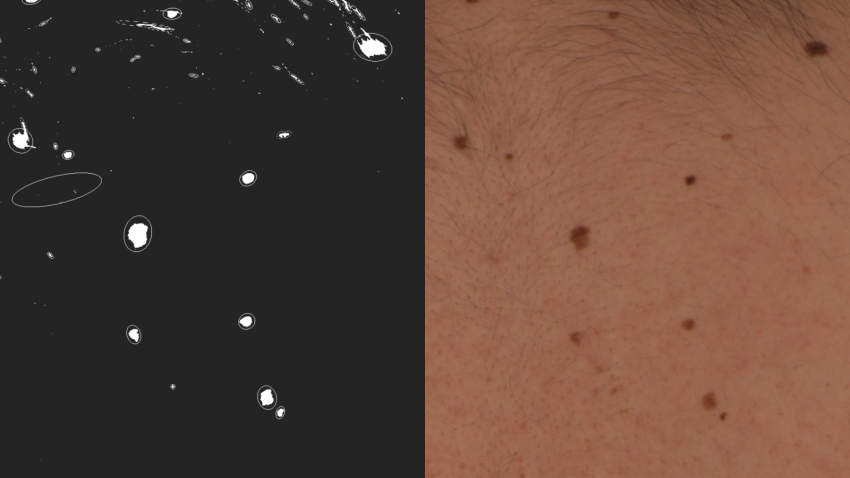

The MoleGazer project aims to combine astronomical data analysis with full body photography used by dermatologists to monitor patients. Within the project, a patient’s skin is treated like the background sky in an astronomical image, and any moles are treated as stars. This analogy allows for automated identification and analysis of moles as they evolve over time.

Caption: A side by side comparison of moles on a patient's back (right) and the same moles as star-like targets in the astronomical software used by the MoleGazer team (left).

Credit: The MoleGazer Team